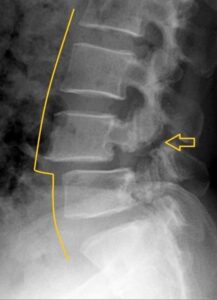

In some children, repetitive spinal stress in sport can lead to a gradual fracture of the bony arch of the vertebrae in their low back. This condition, called spondylo-lysis, is very often undetected, untreated and the fracture remains unhealed for the rest of their lives. This can result in instability, recurring back pain and slippage of the vertebra. (see diagrams)

These stress fractures occur only in children. Usually the problem isn’t discovered until adulthood when X-rays eventually reveal that something occurred when they were younger. The question has often been asked, “Why are we missing them in children?”